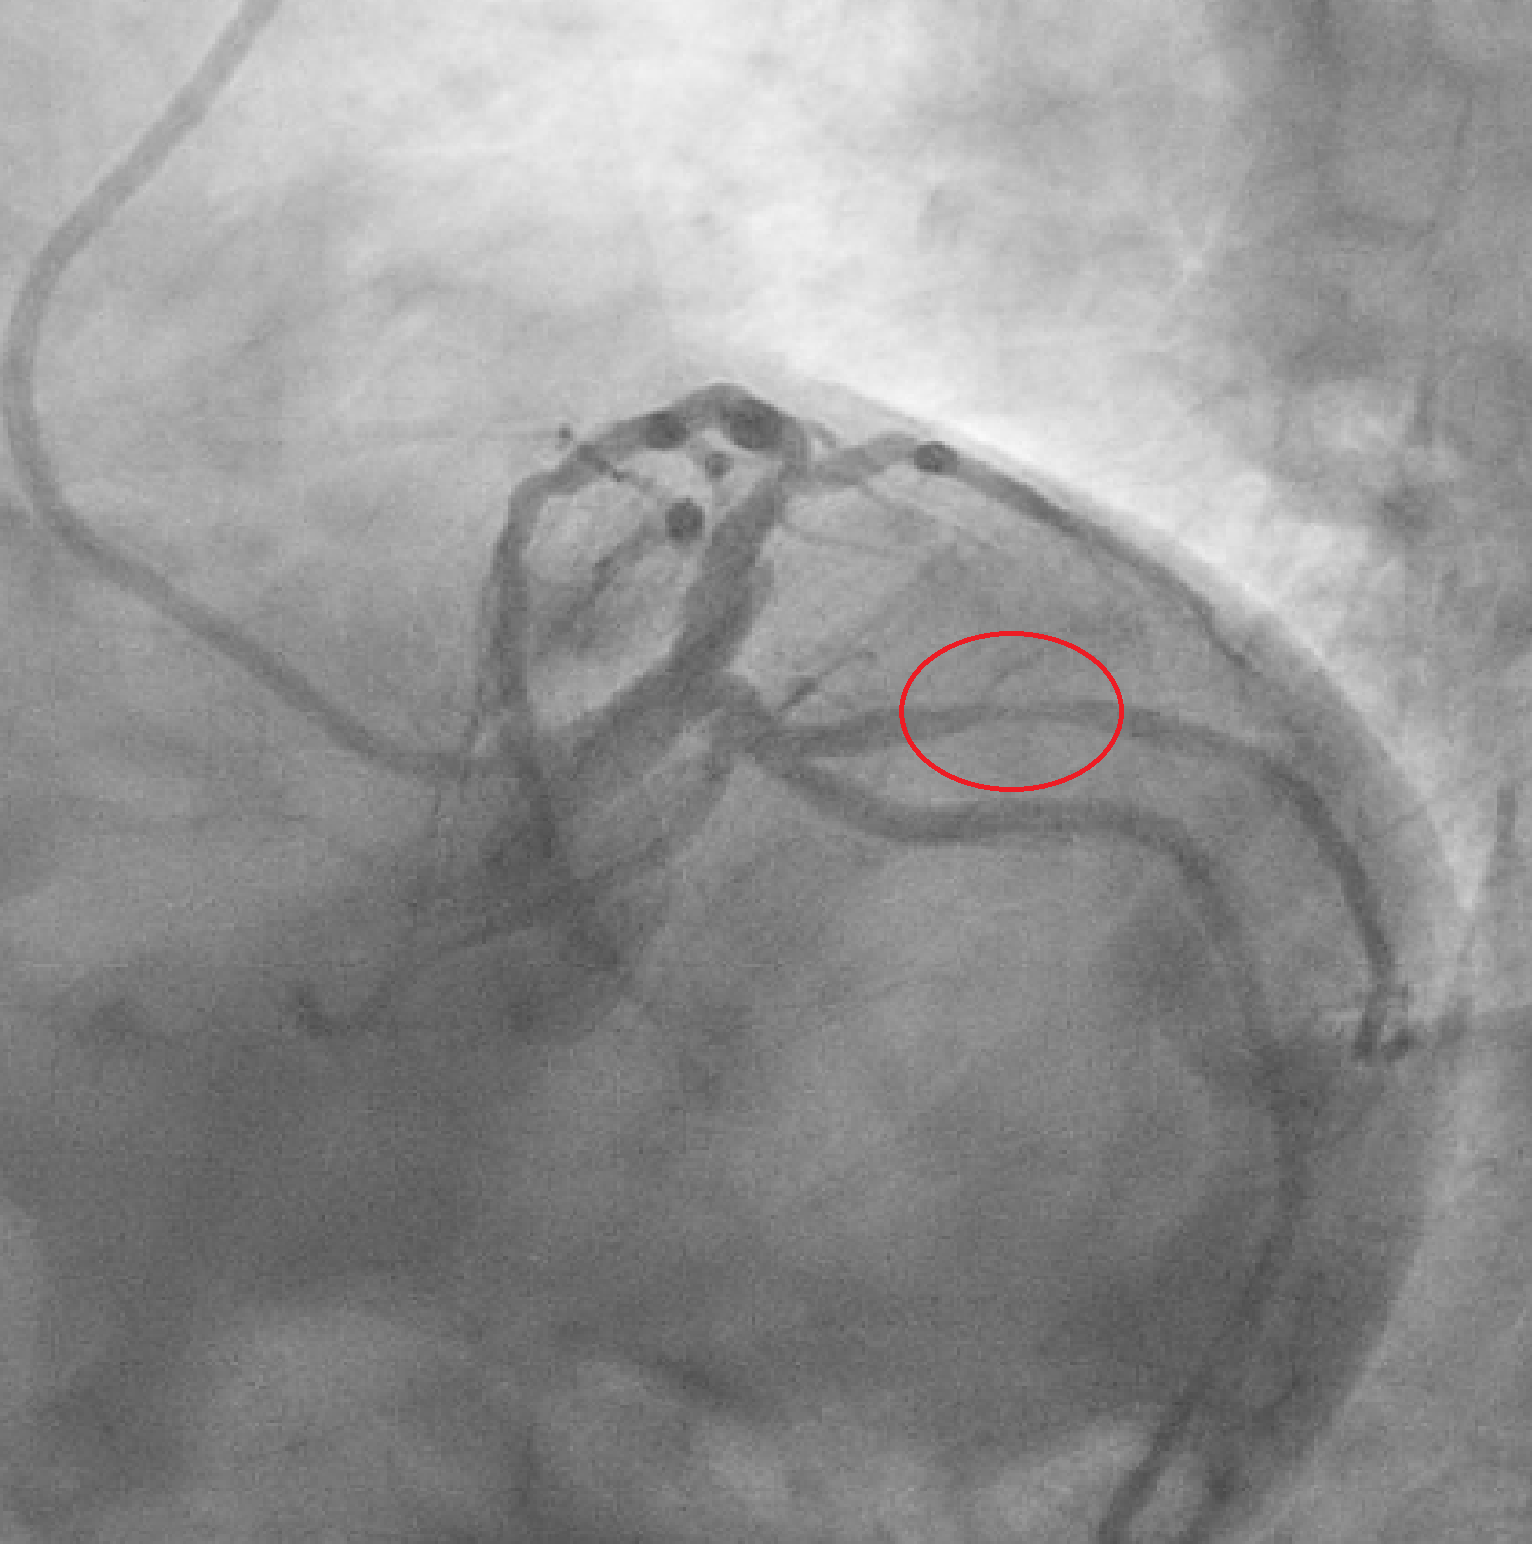

We report the case of a 65-year-old man presenting with chest pain occurring the night before. ECG showed negative T waves in the inferolateral leads. Laboratory revealed rising troponin (0.139 to 0.688 ng/mL). Transthoracic echocardiography demonstrated preserved systolic function without regional wall motion abnormalities (ejection fraction 55%). The day after, complete normalization of the ECG was observed. Patient underwent coronary angiography which revealed an intermediate stenosis of the left anterior descending artery (LAD) not functionally significant (iFR 0.91, FFR 0.87) (Fig. 1). 24-hour Holter ECG monitoring documented episodes of atrial fibrillation. He was discharged on day five with a diagnosis of myocardial infarction with non-obstructive coronary arteries (MINOCA) and referred for cardiac magnetic resonance (CMR). Discharge therapy included Aspirin, Edoxaban and Rosuvastatin/Ezetimibe. Subsequent CMR revealed myocardial edema and late gadolinium enhancement with a transmural ischemic pattern involving the basal inferolateral and anterolateral segments and the apical lateral segment and microvascular obstruction in the basal inferolateral segment, consistent with transmural myocardial infarction (Fig. 2). A subsequent review of the coronary angiogram identified an intermediate, hazy lesion in the proximal circumflex/obtuse marginal branch, compatible with the culprit lesion (Fig. 3). The patient was contacted and clopidogrel 75 mg daily was added, resulting in triple antithrombotic therapy for one month. At 30-day follow-up, the patient remained asymptomatic. This case highlights the pivotal role of CMR in clarifying the diagnosis and guiding therapy in MINOCA, even when the underlying etiology remains uncertain between coronary embolism and unstable plaque.